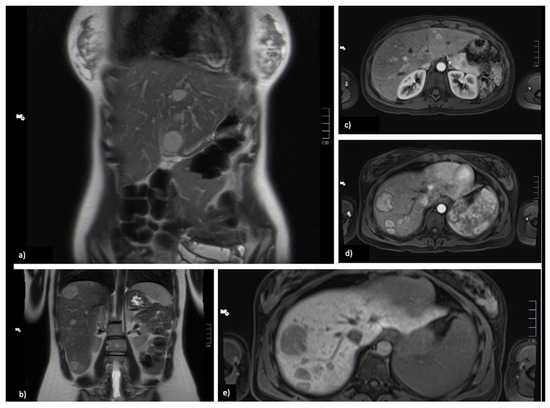

MRI showed hepatomegaly of 19.5 cm in longitudinal diameter, without morphological alterations and with regular borders; the sign intensity was heterogeneous, given the presence of around 40 nodular lesions, dispersed along the parenchyma. The largest lesions were in segment VIII (37 mm), segment II (24 mm) and segment VII (24 mm). They were well-delimited lesions, hyperintense on T2-weighted sequences, practically imperceptible on T1-weighted sequences, one of them with partial loss of signal in the chemical opposition of fat, translating the presence of intracellular fat, with restriction in diffusion but without hyposignal in the ADC map—suggesting benign lesions (Figure 1). There were no other alterations worth of notice.

Figure 1.

Images at diagnosis. (a,b) Coronal T2-weighted image, showing multiple nodular lesions with bilobar distribution, hyperintense on T2-WI. (c,d) On arterial axial T1-weighted GRE 3D FS image, the lesions show high signal intensity compared with surrounding liver parenchyma. (e) axial T1-weighted 3D GRE FS—the lesions are hypointense on 20-min delayed hepatobiliary phase image, with hepatospecific contrast (Gd-EOB-DTPA), because of the lack of normal functioning hepatocytes.